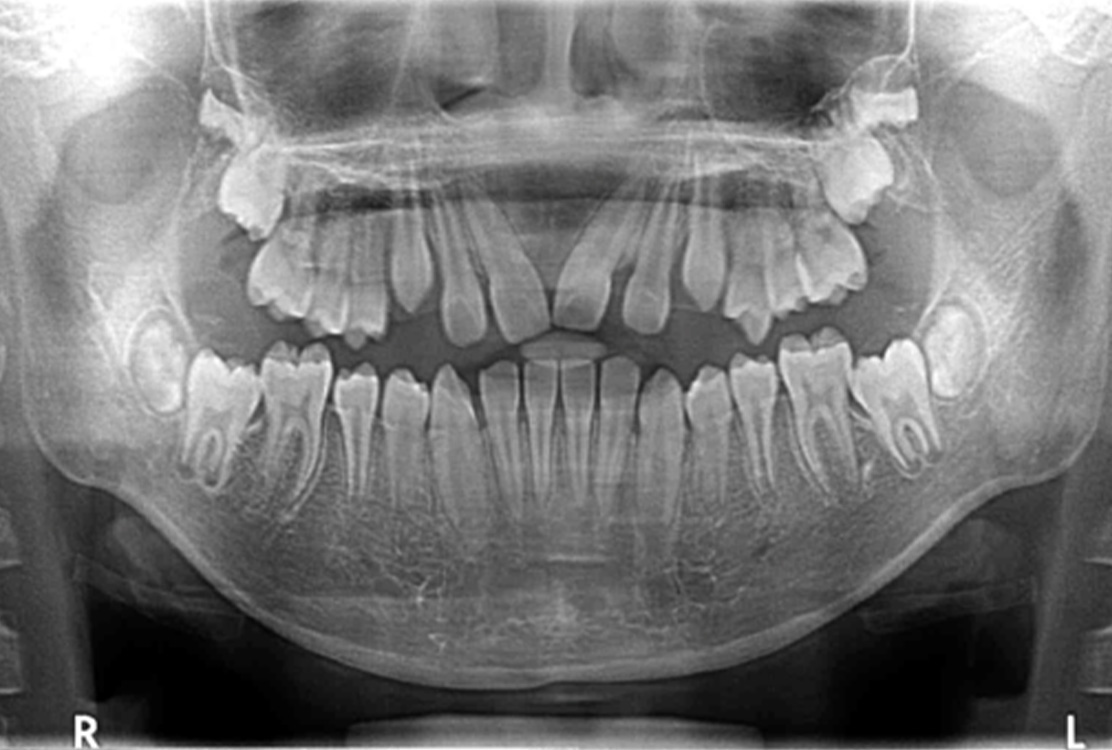

レントゲン画像

治療後